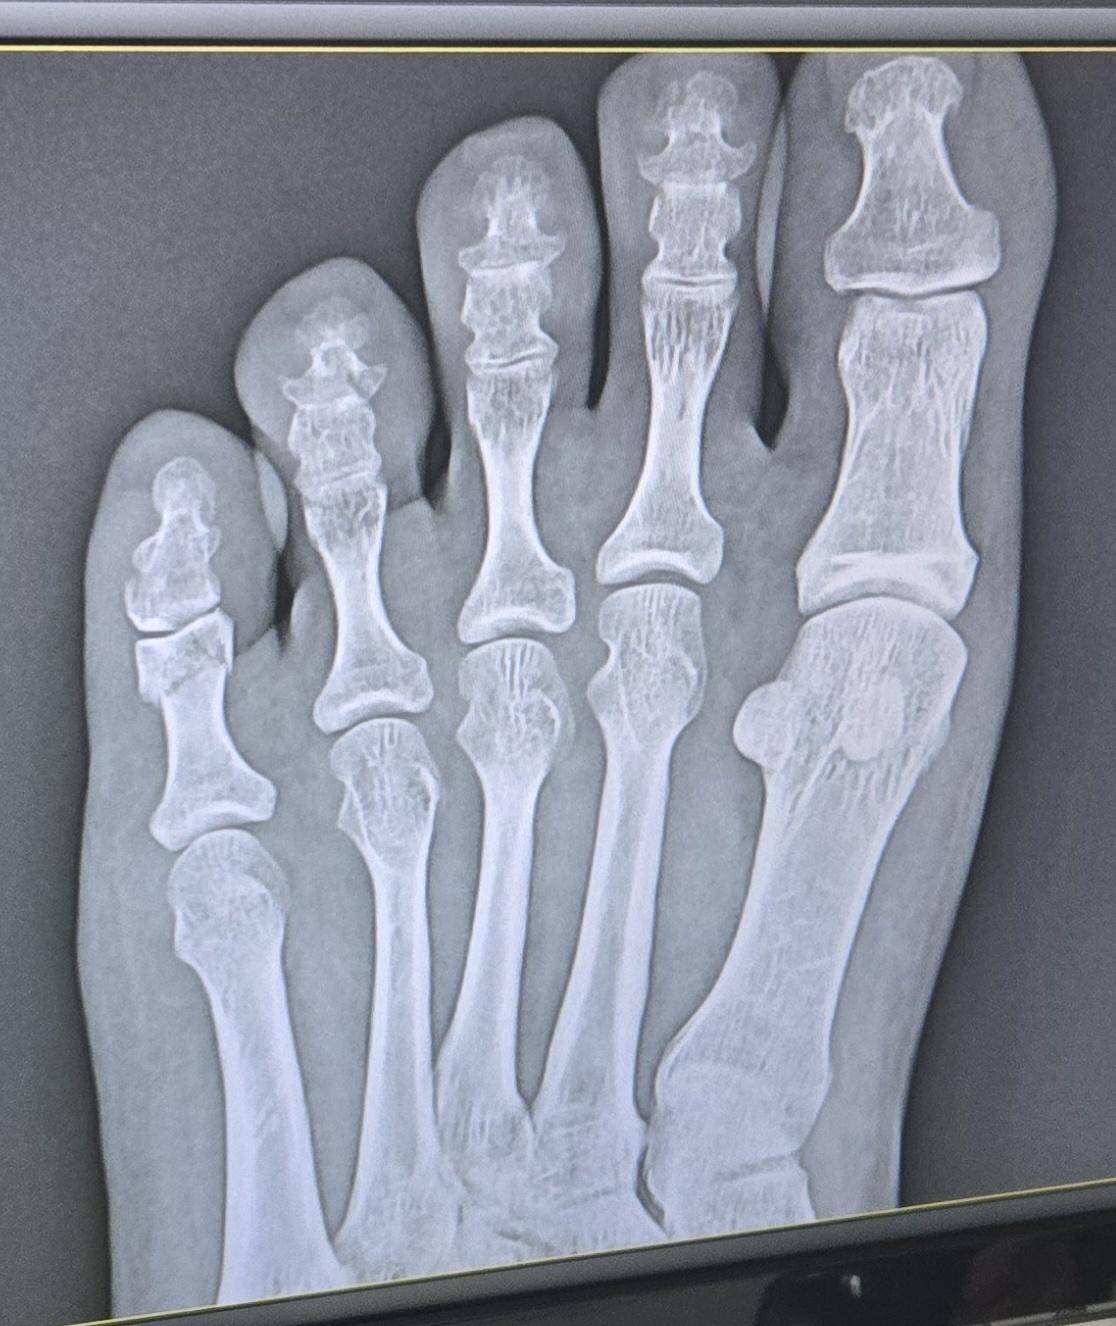

오늘 다른 병원에서 찍은 엑스레이 사진이고 테이핑만 하고 6주 정도는 봐야된다고 하셨어요

Q. 제 상태가 어떤 상태인지 자세히 알고 싶어요. 금 갔다고 하셨는데 측면 사진에서 어긋난 보이는 건 뭔지 특히 궁금합니다!(의사선생님께 자세히 못 여쭈어봐서..ㅜㅜ)

새낄 발가락 골절은 보통 뼈가 크게 벌어지지 않은 금 간 상태라면 수술은 꼭 필요하지 않을 수 있습니다. 또한 엑스레이에서 어긋나 보이는 건 충격으로 미세한 틀어짐인데, 의사 선생님이 수술은 필요 없다고 한 건 기능에 문제 없는 정도라고 판단하신 것 같습니다.

X-ray에서 보이는 어긋난 부분은 골절 부위의 미세한 변위로, 금이 가면서 뼈 조각이 살짝 벌어진 싱태일 수 있습니다.

다행히 큰 어긋남(전위)이 아니라면 수술 없이 테이핑이나 부목 고정으로도 잘 붙을 수 있습니다.

원래 뼈구조이며, 발가락 뼈의 측면을 촬영한 것으로 보입니다.

우선 현재 사진만으론 엑스레이를 확인 할 수 없지만 측면에서 어긋난것으로 보여집니다.